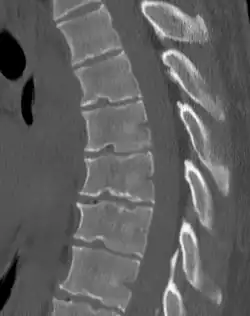

Scheuermann's disease

| Scheuermann's disease | |

| Other names | Scheuermann's kyphosis, Calvé disease, idiopathic juvenile kyphosis of the spine |

| Scheuermann's disease on lateral Xray of the T spine | |

Scheuermann's disease is a skeletal disorder.[3] It describes a condition where the vertebrae grow unevenly with respect to the sagittal plane; that is, the posterior angle is often greater than the anterior. This uneven growth results in the signature "wedging" shape of the vertebrae, causing kyphosis. It is named after Danish surgeon Holger Scheuermann.[4][5][6]

Diagnosis is typically by medical imaging. The degree of kyphosis can be measured by Cobb's angle and sagittal balance.